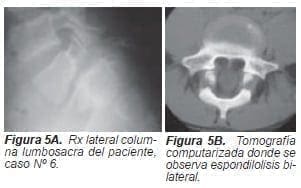

En el caso No 6 se identificó falsa ruta de un tornillo colocado lateral al pedículo de L5, situación manifestada por dolor intratable en el post-operatorio inmediato. La falsa ruta se confirmó mediante rayos X y tomografía computarizada; esta complicación se manejó recolocando el tornillo.